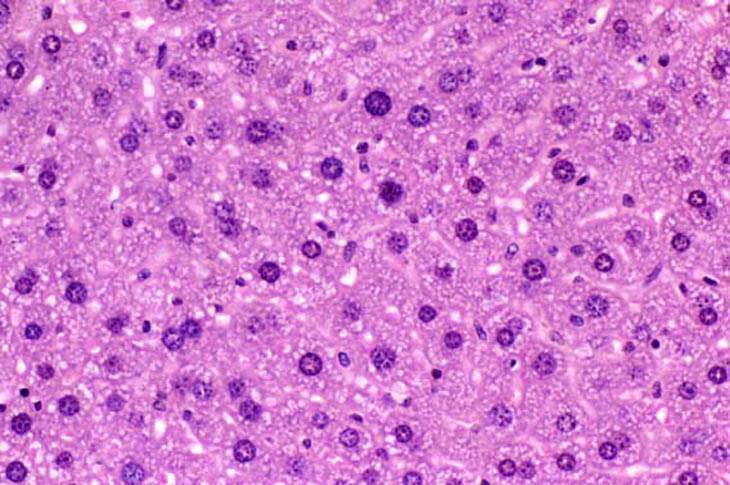

Extreme polyploidy consisting of cytomegalic hepatocytes with very large nuclei as well as cytomegalic hepatocytes with several diploid nuclei is seen in these images from a mouse treated with chlordane for 18 months.